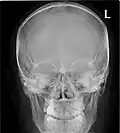

![]() Paranasal sinuses seen in a frontal view | |

Paranasal sinuses are a group of four paired air-filled spaces that surround the nasal cavity.[1] The maxillary sinuses are located under the eyes; the frontal sinuses are above the eyes; the ethmoidal sinuses are between the eyes, and the sphenoidal sinuses are behind the eyes. The sinuses are named for the facial bones and sphenoid bone in which they are located. The role of the sinuses is still debated.

- The maxillary sinuses, the largest of the paranasal sinuses, are under the eyes, in the maxillary bones (open in the back of the semilunar hiatus of the nose). They are innervated by the maxillary nerve (CN V2).[2]

- The frontal sinuses, superior to the eyes, in the frontal bone, which forms the hard part of the forehead. They are innervated by the ophthalmic nerve (CN V1).[2]

- The ethmoidal sinuses, which are formed from several discrete air cells within the ethmoid bone between the nose and the eyes. They are innervated by the ethmoidal nerves, which branch from the nasociliary nerve of the ophthalmic nerve (CN V1).

- The sphenoidal sinuses, in the sphenoid bone. They are innervated by the ophthalmic and maxillary nerve (CN V1 and V2).[2]